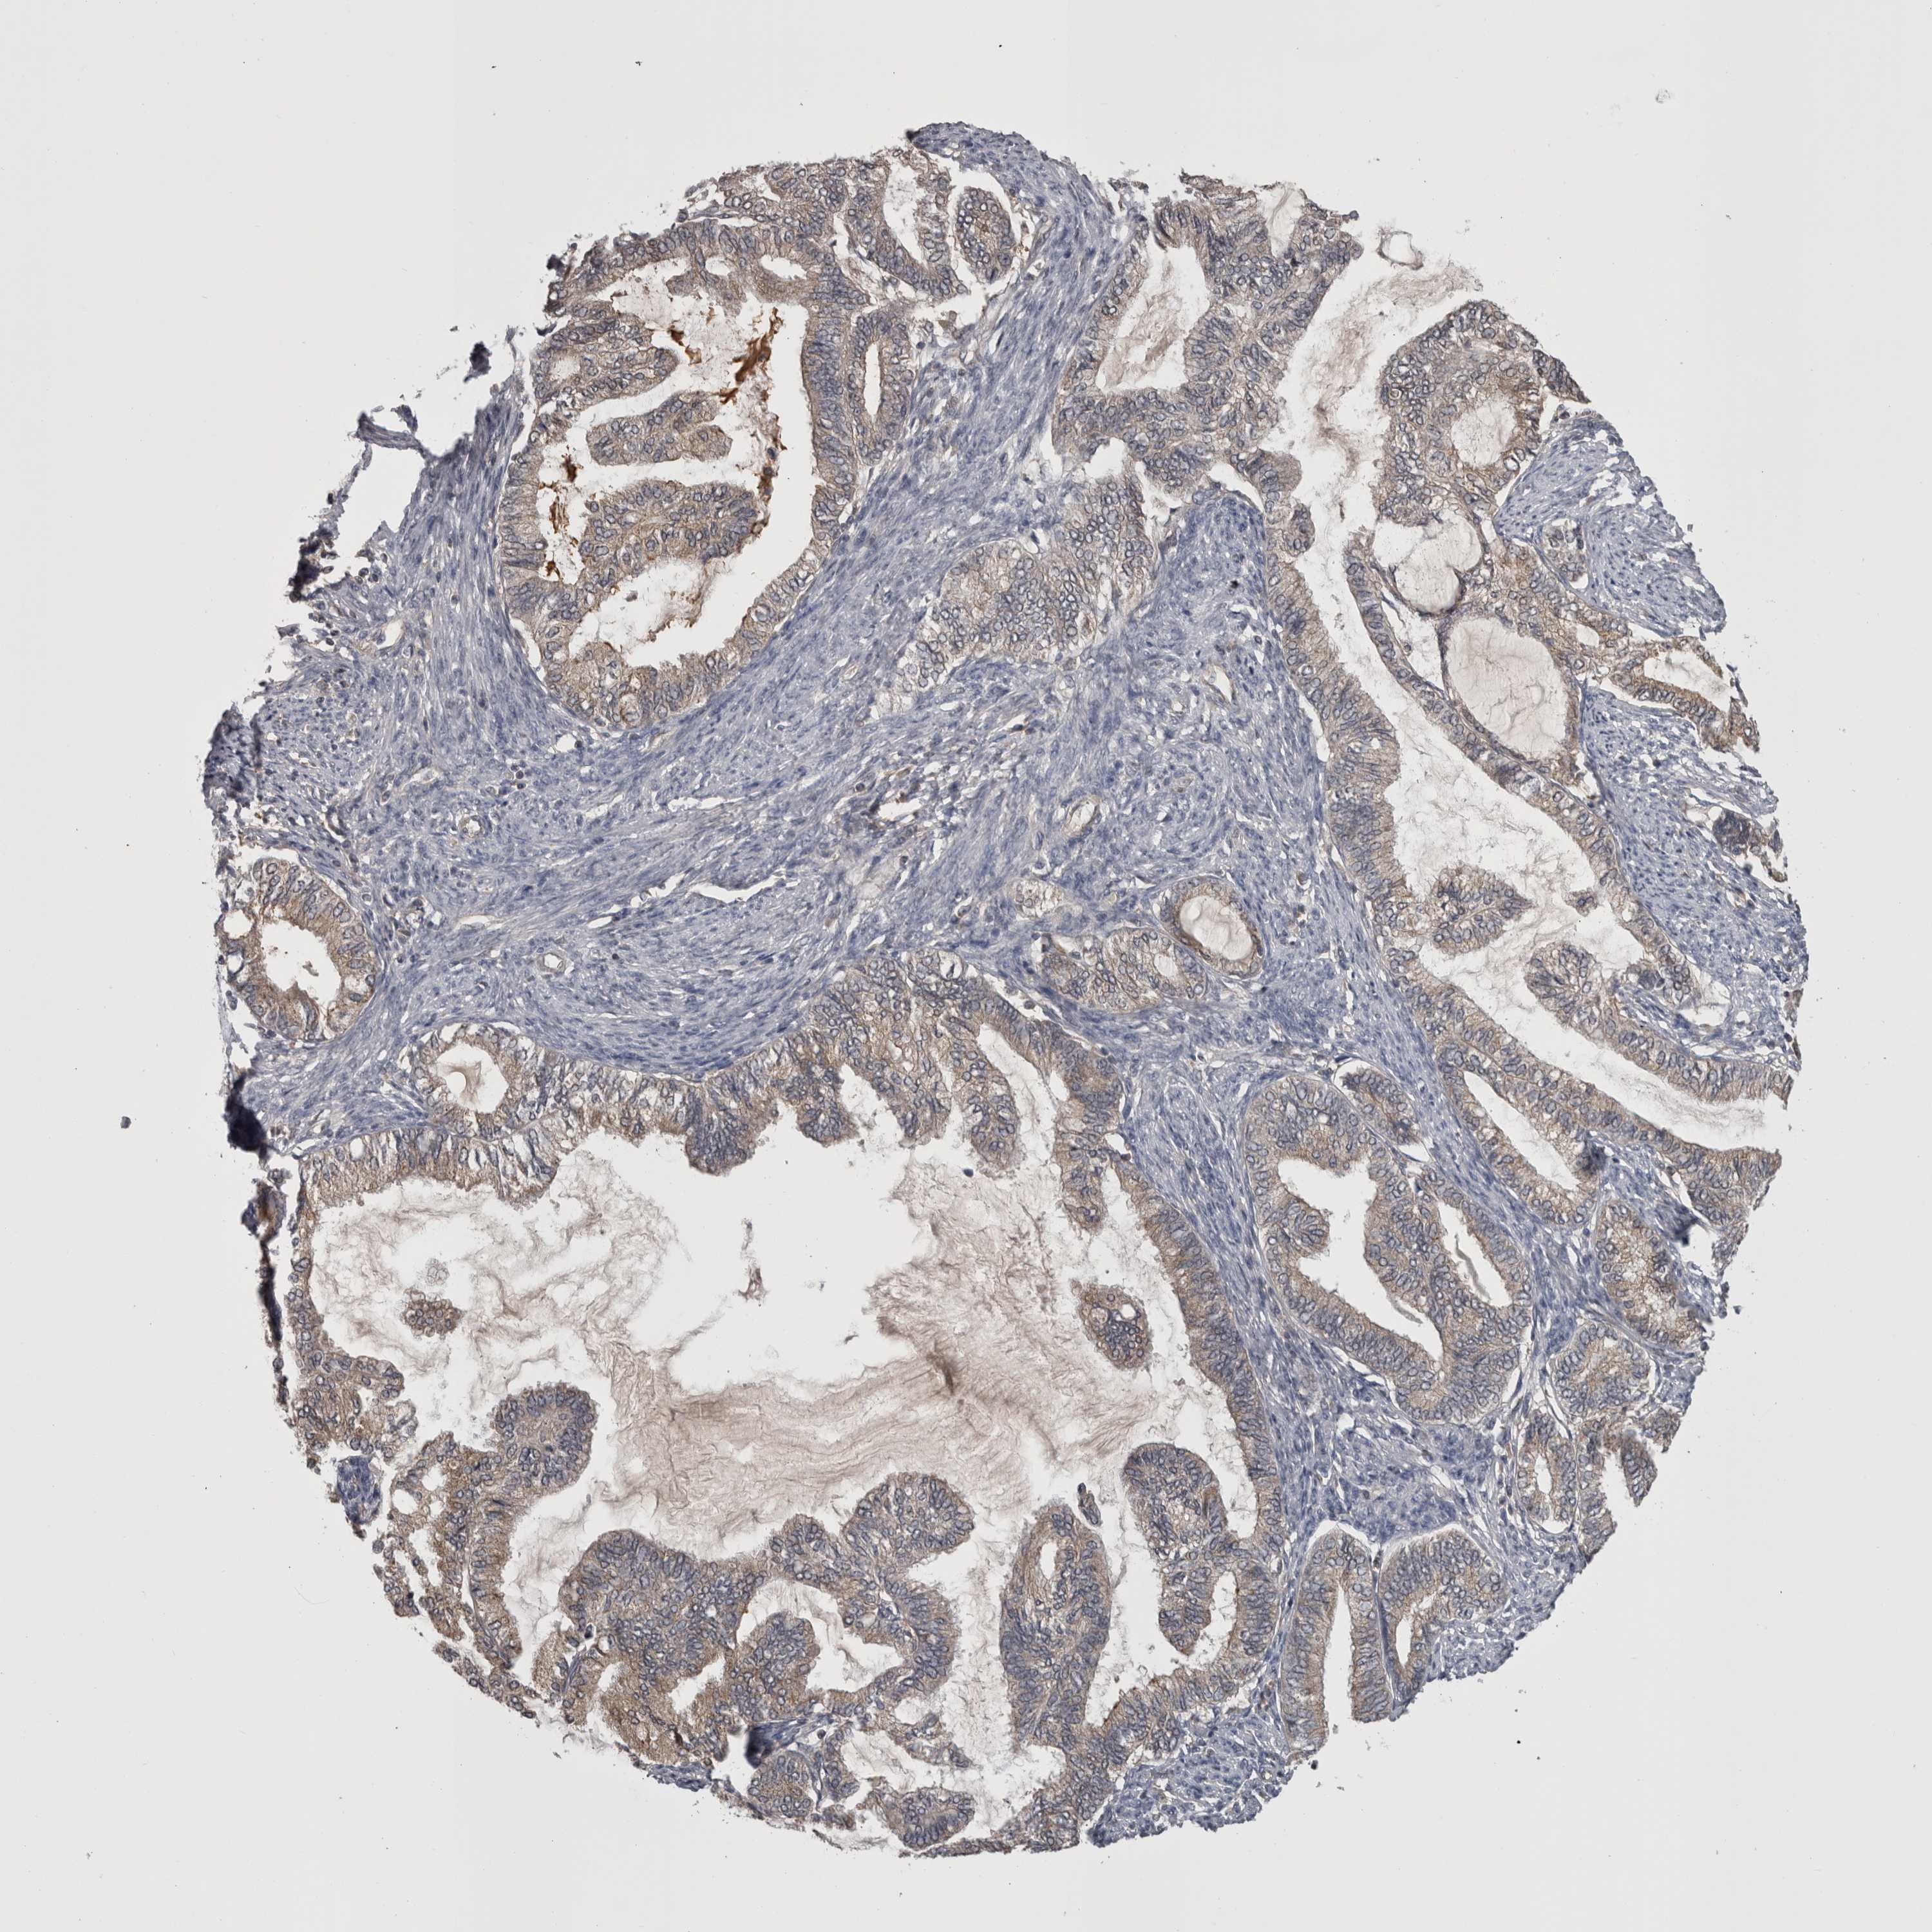

ENDOMETRIAL CANCER - Protein expressioni

A mouse-over function shows sample information and annotation data. Click on an image to view it in a full screen mode. Samples can be filtered based on level of antibody staining by selecting one or several of the following categories: high, medium, low and not detected. The assay and annotation is described here.

Note that samples used for immunohistochemistry by the Human Protein Atlas do not correspond to samples in the TCGA dataset.

Antibody stainingi

Antibody staining in the annotated cell types in the current human tissue is reported as not detected, low, medium, or high, based on conventional immunohistochemistry profiling in selected tissues. This score is based on the combination of the staining intensity and fraction of stained cells.

Each image is clickable and will lead to virtual microscopy that enables deeper exploration of all samples and also displays staining intensity scores, fraction scores and subcellular localization as well as patient and tissue information for each sample.

Antibody HPA026681

Staining

High

Medium

Low

Not detected

Intensity

Strong

Moderate

Weak

Negative

Quantity

>75%

75%-25%

<25%

None

Location

Nuclear

Cytoplasmic/membranous

Cytoplasmic/membranous,nuclear

Adenocarcinoma, NOS

Adenocarcinoma, metastatic, NOS